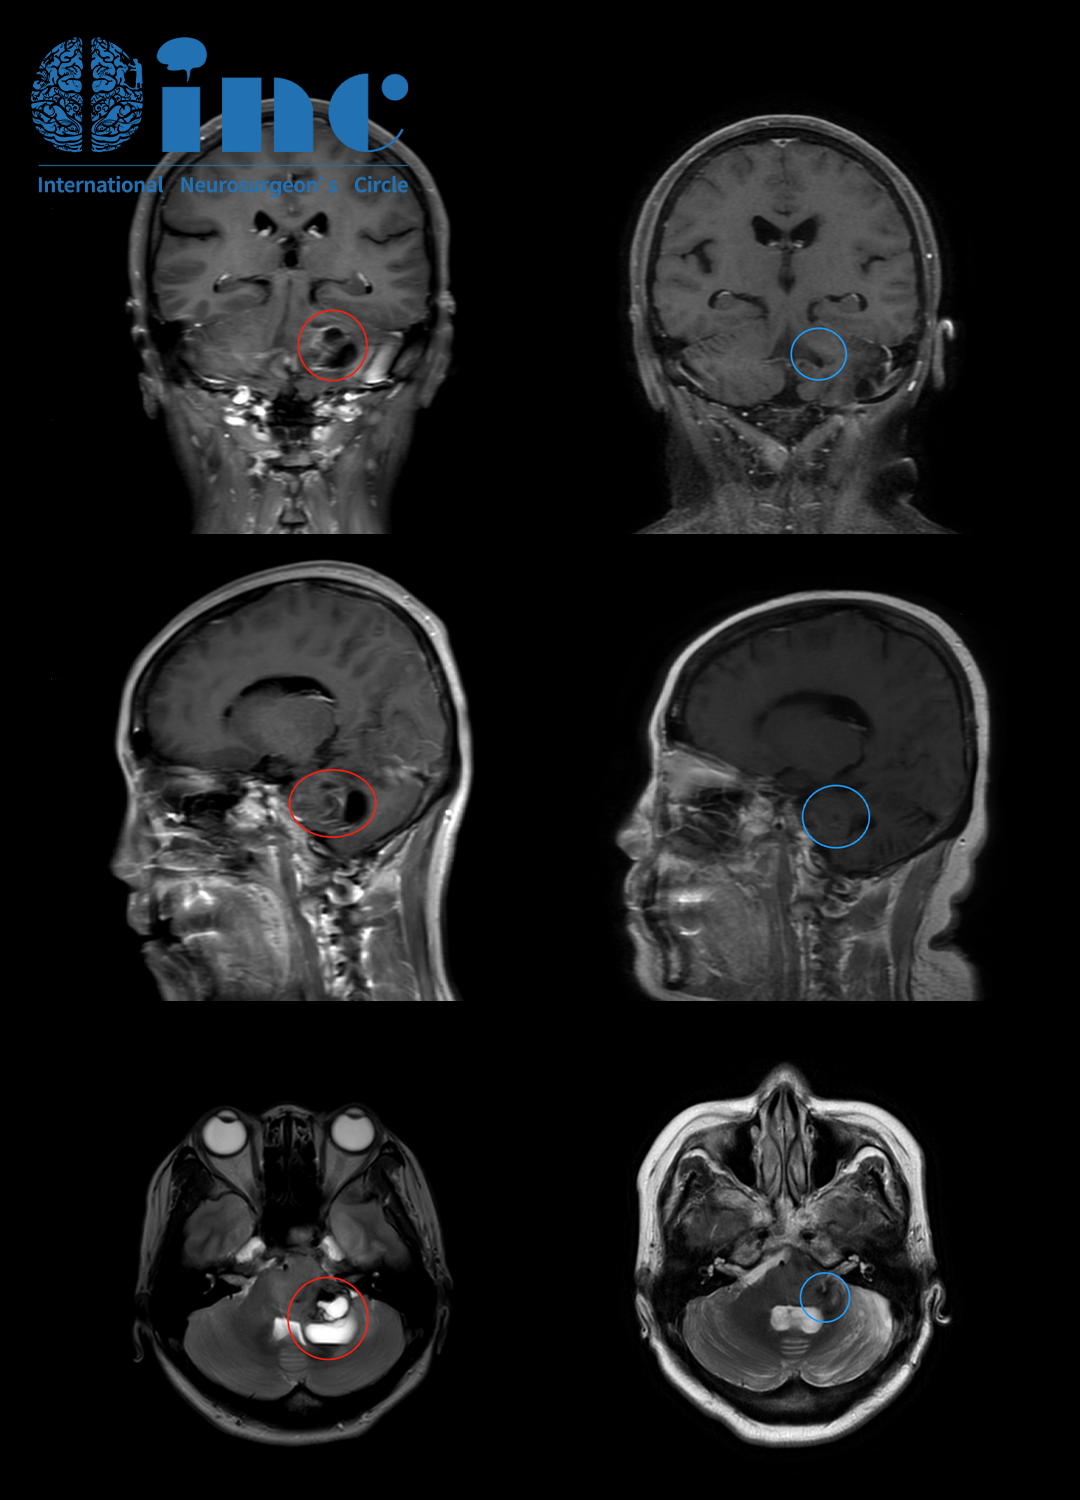

吴女士术前(红色)和术后四个月(蓝色)MRI对比

术后情况:手术结束后,患者转入重症监护病房进行观察。除了术前的复视、轻度的面神经麻痹和共济失调步态以外,没有新的神经功能缺损。

术后第2天:CT 影像示正常术后表现,病人被转回神经外科病房。她在康复治疗师 的指导下开始缓慢活动。住院期间,复视和面神经麻痹持续存在,但有所改善。步态在术后期间得到稳定。核磁检查证明该内生型肿瘤得到了大约90%的切除。

术后3个月回访:

巴教授表示质子治疗和化疗有了积极的作用。吴女士有了明显的改善,肿瘤缩小,特别是没有进一步扩大。在目前的情况下,这是我们到目前为止通过手术和辅助治疗所能达到的最好效果。不过我们可以预计,联合放化疗,特别是质子治疗将在未来6个月内进一步发挥其作用,并可能导致剩余肿瘤的缩小,同时临床效果也应该变得更加明显。目前出现的临床症状也会在未来几个月内有所改善。对于患者的康复训练,巴教授也提出了他的建议,应集中在平衡训练上。